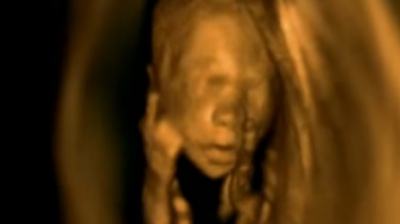

Ce fac bebeluşii cât timp stau în burta mamei? Dacă ești femeie și ai fost ori ești însărcinată, atunci cu siguranță știi că micuții spre sfârșitul sarcinii sunt uneori foarte activi în burtă, astfel încât ai impresia că ei joacă acolo fotbal sau fac ceva de genul acesta.